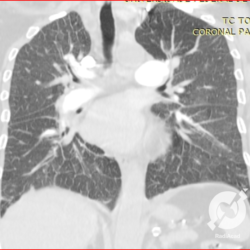

Opacidades em vidro fosco, espessamento septal liso, proeminência de estruturas venosas e derrame pleural bilateral.